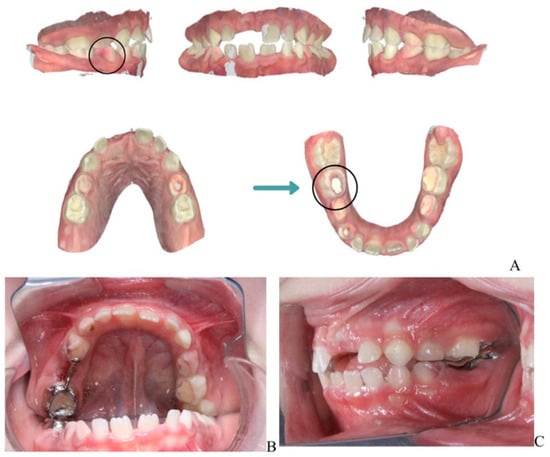

Figure 5 illustrates the post-treatment intraoral condition of the patient. Regression of the previously noted fistulas is evident, and the gingival tissues appear healthy with no signs of inflammation. This demonstrates the effectiveness of the staged dental interventions and ongoing management.

Figure 5.

Post-treatment intraoral view showing regression of fistulas and stable gingival health. (A) Intraoral frontal view in occlusion. (B) Occlusal view of the maxilla.